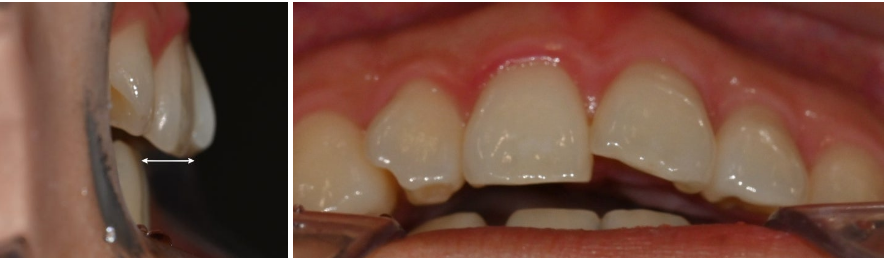

23.10.20

교합면을 보았을 땐

아래 앞니 2개가 결손되어 있으며

사이 공간이 있습니다.

위아래 앞니 사이 거리가 과도합니다.